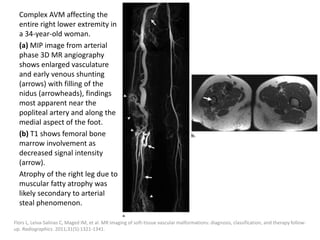

immediately, but after 4-6 weeks.

Ravindranathan H, Gillis J, Lord DJ. Intensive care experience with sclerotherapy for cervicofacial lymphatic malformations. Pediatr Crit

Care Med 2008; 9: 304–309

Capillary Malformation

Incidence

Clinical presentation

Imaging features

Treatment

Present at birth in around 0.3% of children.

Traditionally named port-wine stains, they are

the least common and the most superficial of